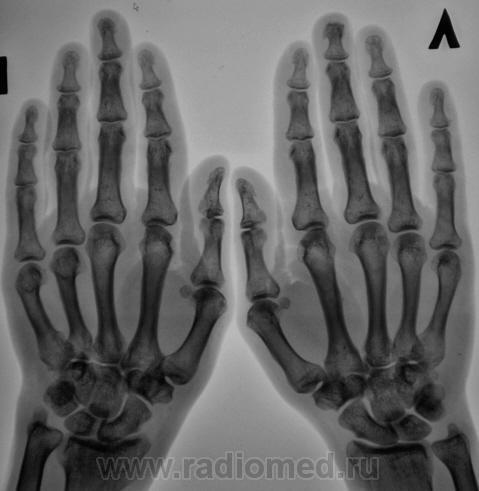

Пол пациента: Женский пол Тип патологии: Другое Область исследования: Скелетно-мышечная система Методы исследования: Rg Пациент с диагнозом "ревматоидный артрит" направлен на рентгенографию кистей. https://radiomed.ru/sites/default/files/styles/case_slider_image/public/user/12/2.pb100037a.jpg?itok=yFjpd1IX https://radiomed.ru/sites/default/files/styles/case_slider_image/public/user/12/3.pb100038.jpg?itok=92itQ56R https://radiomed.ru/sites/default/files/styles/case_slider_image/public/user/12/4.pb100038a.jpg?itok=rsA7mSo8 ID:8677 Чт, 11/11/2010 - 01:03 #1 Makcimalist Не на сайте Был на сайте: 11 лет 8 месяцев назад Зарегистрирован: 08.05.2010 - 14:28 Публикации: 1994 - специфич. признаков начальных стадий РА не нашёл... -------------- "Просто, по видимости, не видеть логики в очевидных вещах - это тоже одно из свойств некоторых умов, наряду с грустными думами о свойствах ума других." © Vega 08/10/2011 Чт, 11/11/2010 - 14:44 #2 Катенёв Валенти... Не на сайте Был на сайте: 7 лет 2 недели назад Зарегистрирован: 22.03.2008 - 22:15 Публикации: 54876 Норму писать? Сб, 13/11/2010 - 01:28 #3 Makcimalist Не на сайте Был на сайте: 11 лет 8 месяцев назад Зарегистрирован: 08.05.2010 - 14:28 Публикации: 1994 Начальные проявления остеоартроза пястно-фаланговых,м/фаланговых суставов... (Норма бывает п/е рождения... и то не всегда...) -------------- "Просто, по видимости, не видеть логики в очевидных вещах - это тоже одно из свойств некоторых умов, наряду с грустными думами о свойствах ума других." © Vega 08/10/2011 Сб, 13/11/2010 - 19:53 #4 Глазков Игорь А... Не на сайте Был на сайте: 9 месяцев 2 недели назад Зарегистрирован: 19.12.2008 - 20:41 Публикации: 1597 Имеются кистовидные просветления костной ткани в эпифизах костей. Прийди к Себе

- специфич. признаков начальных стадий РА не нашёл...

Начальные проявления остеоартроза пястно-фаланговых,м/фаланговых суставов...

Имеются кистовидные просветления костной ткани в эпифизах костей.